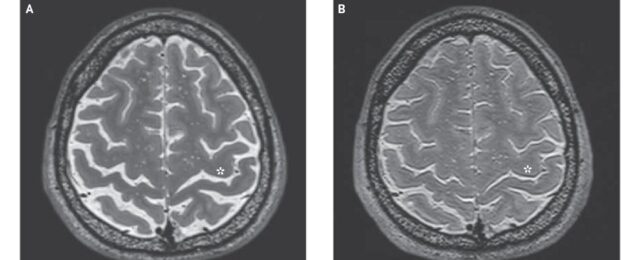

Here's What Long-Term Living in Space Does to Astronaut Brains

As if astronauts didn't have enough to worry about, a new study has confirmed one more possible health problem intrepid spacefarers face as they reach for the stars – tissue expansion at the top of the brain.

It's not clear yet what the consequences of this swelling might be, and if there are any adverse health effects at all. But it's hard to imagine 'brain squeeze' is something potential Martian pioneers would be looking forward to.